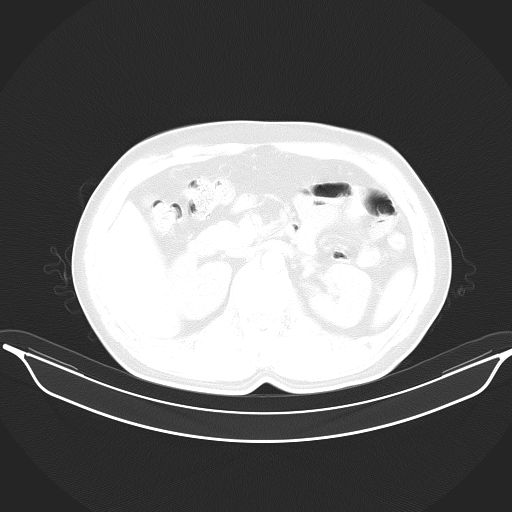

标题: CT25490:男,40岁,体检发现;无其它不适。 [打印本页]

标题: CT25490:男,40岁,体检发现;无其它不适。

考虑:1、过各敏性肺炎可能性大,建议定期复查。

2、轻度脂肪肝。

考虑右下肺周围性肺癌并肺内多发转移,纵隔淋巴结转移!

支持 !考虑右下肺周围性肺癌并肺内多发转移,纵隔淋巴结转移,(气管前腔静脉后,隆突下,主动脉弓下都有了)